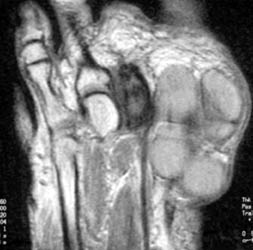

47 year old male with a 6 x 3.5 cm lobulated mass along plantar medial aspect of the 1st toe, which is hypointense on T1W and hyperintense On T2W images. Scattered small foci of hypointensity, representing calcifications is present on all the sequences. The soft tissue mass with small calcifications is also seen on the plain radiograph.